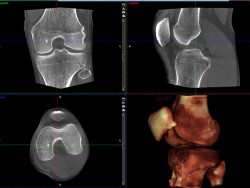

Mit den Aufnahmen des Digitale Volumentomograph der Firma SCS gewinnt der behandelnde Arzt Dank der ultrahochauflösenden Darstellung von Hartgewebestrukturen, nach nur wenigen Sekunden Aufnahmezeit, eine Diagnostiklösung auf dem neuesten Stand der Technik. Selbst feinste Brüche in den Extremitäten werden sichtbar. Durch die speziell entwickelte Positionierstütze wird sichergestellt, dass sich das zu untersuchende Körperteil immer genau im Sichtfeld befindet. Zudem ist für Extremitäten eine Aufnahme unter Belastung möglich, bei welcher der Patient während der Bildaufzeichnung in der Gantry steht. Eine Belastungsaufnahme des Fußgelenks oder Knies zeigt die Anatomie bei natürlicher Belastung.

Bildgebung des offenen CTs

Eine Belastungsaufnahme des Fußgelenks oder Knies zeigt die Anatomie bei natürlicher Belastung.